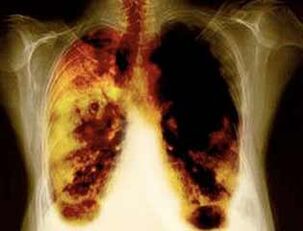

- Reducindo o risco de desenvolver cancro de pulmón e moitos outros tipos de cancro.

- Reducir o risco de desenvolver certas enfermidades pulmonares (por exemplo, enfermidade pulmonar obstructiva crónica).

- 10 anos despois do cesamento do tabaquismo nun 40%, a probabilidade de cancro de pulmón diminúe un 40%.